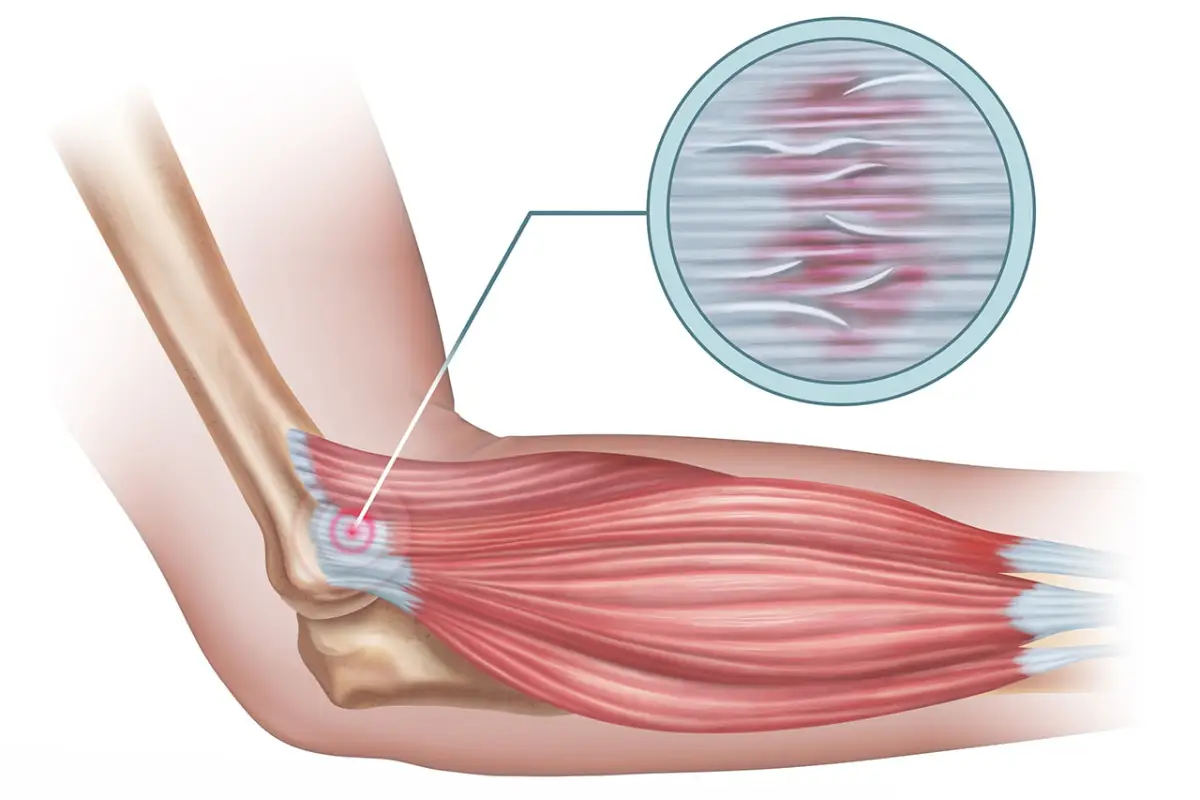

Tennis elbow, also known as lateral epicondylitis, is a painful elbow ailment. It’s a type of overuse injury that’s caused by repetitive motions. When the tendons in the forearm that allow for backward wrist bending become inflamed, the disease develops. With this disease, lifting or bending the arm, twisting or stretching the forearm, and grasping motions can produce considerable pain. Tenderness can radiate from the elbow to the forearm, and in some cases, all the way to the wrist.

Tennis elbow is almost often the result of an underlying problem that can only be discovered following a thorough examination that includes imaging studies. In the best-case scenario, the medication you take to self-treat will simply mask the pain while failing to address the underlying cause of your injury. Tennis elbow can’t be cured with a topical treatment.